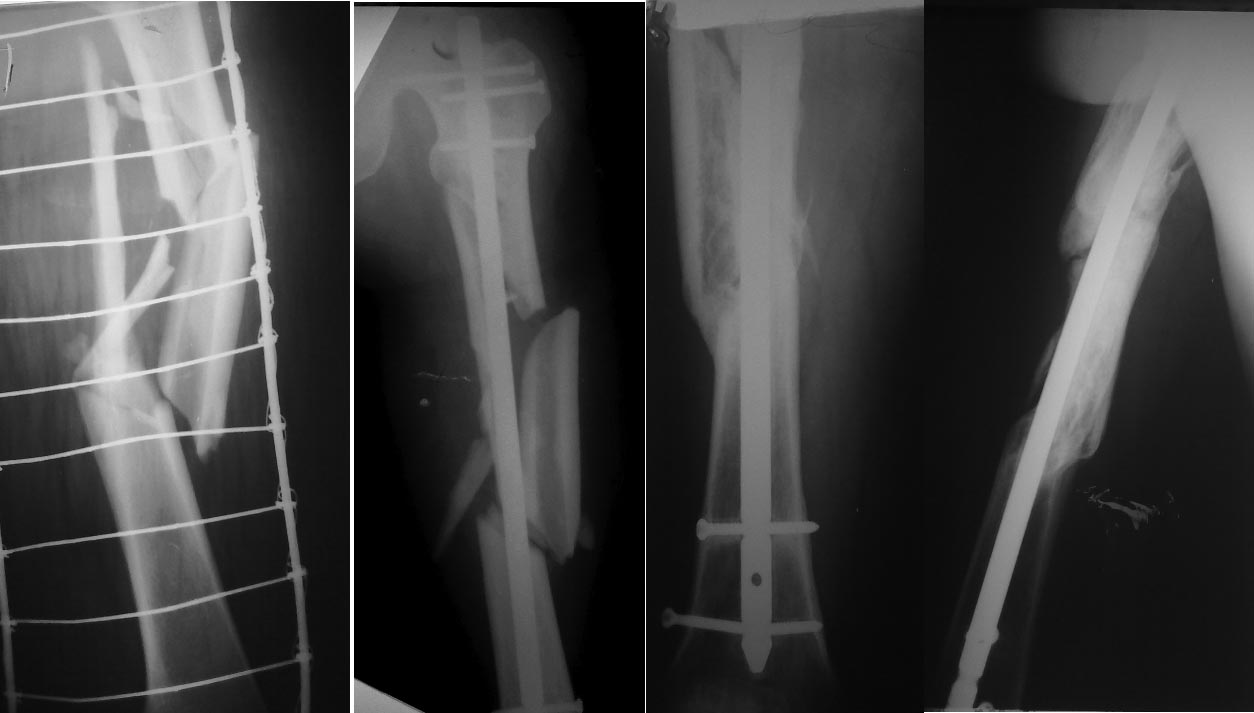

Итоги лечения многооскольчатого перелома бедра

Делюсь отдаленным результатом лечения многооскольчатого перелома бедра (случай публиковался на форуме в феврале 2016

В феврале сделана костная аутопластика (расщеп малоберцевой кости + крыло подвздошной кости) + аллопластика + PRF. От динамизации убежал.

На сейчас: жалоб нет, полная нагрузка, спорт. Травма 26.09.2015, закрытая репозиция, БИОС PFNA Long 28.09.2015, февраль 2016 - костная пластика. Ссылка на медиаресурс http://dropmefiles.com/vTXbx